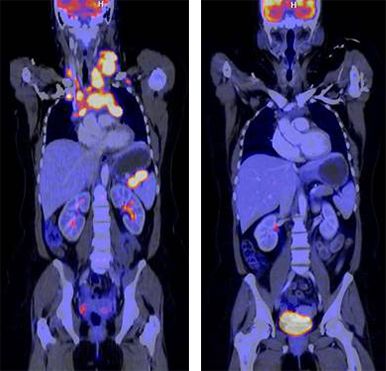

FDG-PET/CT, Mb. Hodgkin, vor/nach Chemotherapie

Die Methoden der Hybrid-Bildgebung (PET/CT und PET/MRT) gehören zu den modernsten bildgebenden Verfahren und werden insbesondere zur Tumordiagnostik eingesetzt. Der große Vorteil der Hybrid-Bildgebung ist die Kombination einer funktionellen Methode (PET, Positronen-Emissions-Tomographie) mit einer morphologischen Bildgebung (CT - Computertomographie oder MRT - Magnetresonanztomographie) in einem Untersuchungsgang. Man erhält so gleichzeitig Informationen über Funktionen (z.B. Stoffwechsel) und zu Strukturen von gesundem oder krankem Gewebe im Körper.

Die PET ermöglicht mit hoher Sensitivität und Spezifität kleinste Stoffwechselveränderungen nachzuweisen. Hierfür werden schwach radioaktiv markierte Substanzen (sogenannte Radiopharmaka) eingesetzt, die spezifisch Stoffwechselveränderungen von Erkrankungen nachweisen oder gegen Antigene gerichtet sind. PET ist damit die genaueste Methode, um nicht-invasiv molekulare Veränderungen abzubilden.

Am Universitätsklinikum Tübingen wird seit 2022 eines der weltweit ersten PET/CT-Geräte mit einem erweiterten Gesichtsfeld von 106 cm betrieben. Der sogenannte Ultralong-FOV-PET/CT wird im Vergleich zu den derzeit zur Verfügung stehenden PET/CT-Geräten mit einer 10-fach höheren Sensitivität und einer erheblich verbesserten Orts- und Zeitauflösung einher, was eine bislang unerreichte Bildqualität zum Nachweis von beispielsweise kleinster Tumorläsionen im frühen Stadium ermöglicht. Diese Neuentwicklung kann damit als Meilenstein in der molekularen Bildgebung angesehen werden.